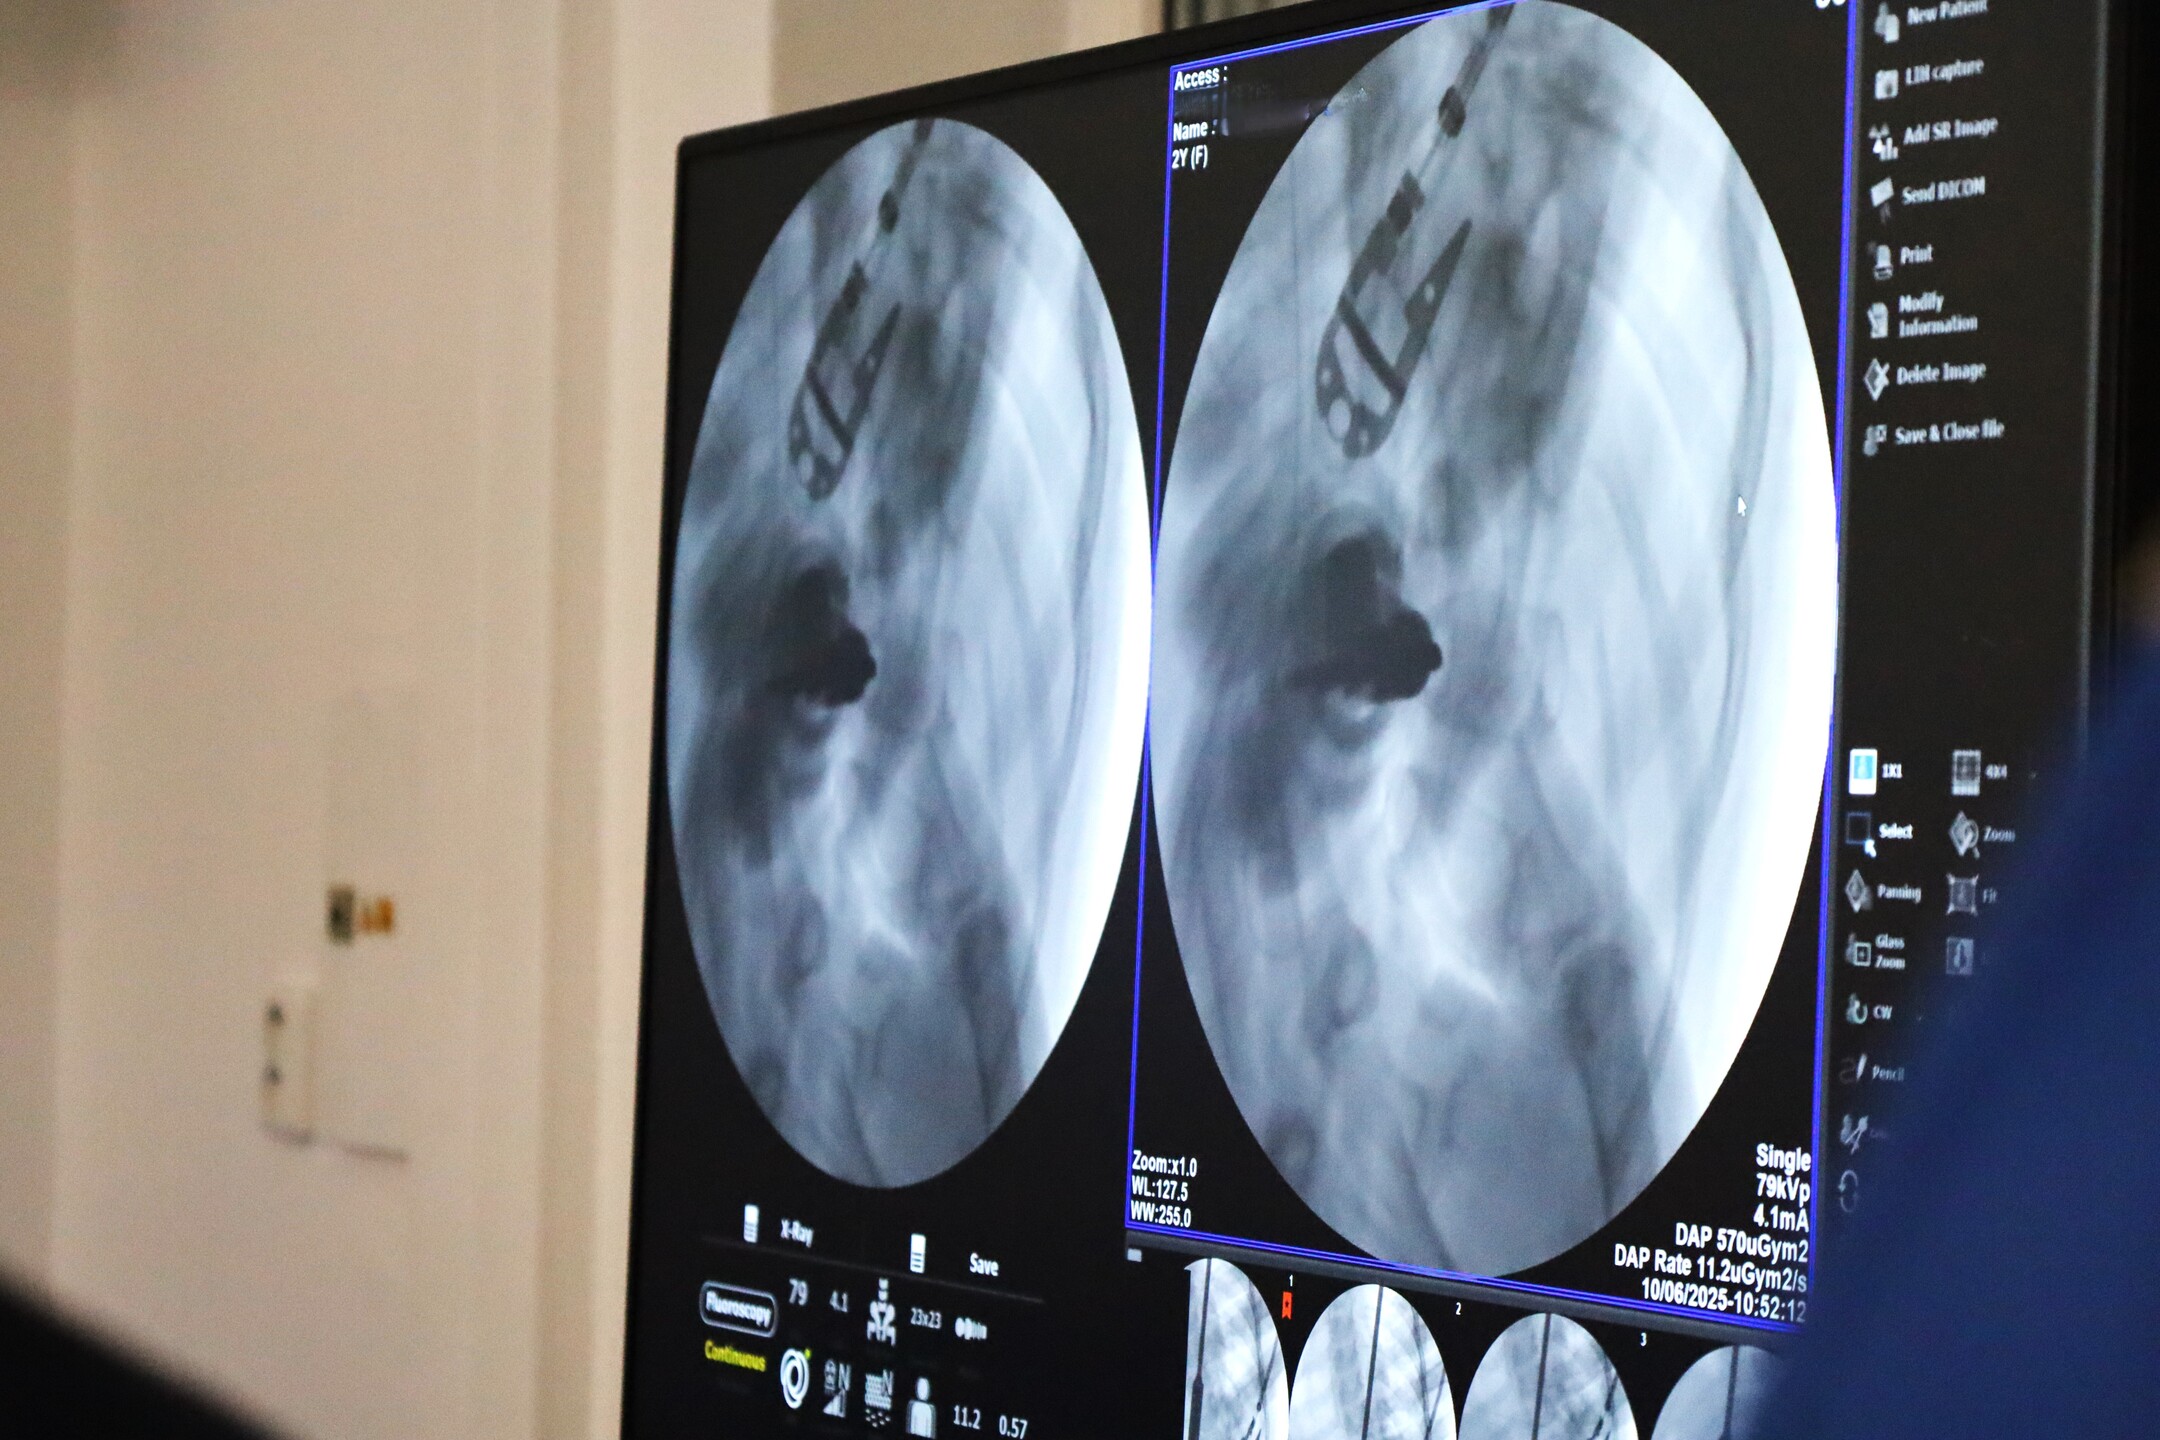

Lekári oddelenia pediatrickej ortopédie a spondylochirurgie žilinskej nemocnice zrealizovali úspešný zákrok u 2-ročného dieťaťa s extrémne ťažkou idiopatickou infantilnou skoliózou. Náročnú diagnózu, ktorá vznikla po narodení a je mimoriadne vzácna, nebolo možné vyriešiť konzervatívnou liečbou. Žilinskí odborníci vykonali operáciu ako prví na Slovensku.

Idiopatické skoliózy sú najčastejším druhom skolióz spomedzi detských deformít chrbtice a ich vznik je typický pre predpubertálny vek. Liečba je vo väčšine prípadov konzervatívna, no ťažké prípady je potrebné operovať, zvyčajne po ukončení rastu dieťaťa. „Výskyt diagnózy v tak nízkom veku, aký mala operovaná pacientka, je mimoriadne vzácny, pričom skolióza postihla celú chrbticu. Takýto prípad sa na Slovensku ešte neoperoval a bola to pre nás veľká výzva,“ uviedol primár Oddelenia pediatrickej ortopédie a spondylochirurgie FNsP Žilina Juraj Popluhár s tým, že chrbtica si u malého dieťaťa vyžadovala aplikáciu dlhého, jemného fixátora, ktorý s ním musí rásť. „Chcem vyjadriť veľké uznanie a vďaku celému tímu oddelenia za ich profesionálnu prácu a mimoriadne nasadenie. To, čo naši odborníci dokázali aj počas tejto operácie je dôkazom ich neoceniteľných zručností na najvyššej úrovni. Žilinské pracovisko je pod vedením Juraja Popluhára lídrom v oblasti pediatrickej spondylochirurgie na Slovensku. Každý krok, ktorý podniká, posúva hranice medicíny a prináša pacientom v ťažkých životných situáciách príležitosť na lepšiu budúcnosť,“ doplnil riaditeľ FNsP Žilina Juraj Kacian.